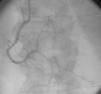

The authors present the case of an 83-year-old male with a history of hypertension, appendectomy and cervical spine surgery who presented at the emergency department with epigastric pain and dyspnea at rest for six hours. The physical examination was compatible with refractory acute pulmonary edema requiring endotracheal intubation and ventilation. The electrocardiogram showed sinus rhythm with ST-segment elevation in the inferior leads. The emergent coronary angiography revealed three-vessel disease with distal occlusion of the right coronary artery (Figure 1, Videos 1 and 2). Primary angioplasty was performed successfully (Figure 2, Video 3). During the procedure a contrast retention image was observed apparently synchronous with the cardiac/respiratory cycle (Figure 3, Video 4). The first possibility that came to mind was an aortic dissection, which was excluded by an anteroposterior projection, which showed that the image was in the midline (Figure 4, Videos 5 and 6). A chest computed tomography scan was then requested to rule out the presence of a fistula (esophageal or bronchial), which revealed that the image corresponded to retention of contrast in the medullary canal from myelography performed in the 1980s (Figure 5A and B).